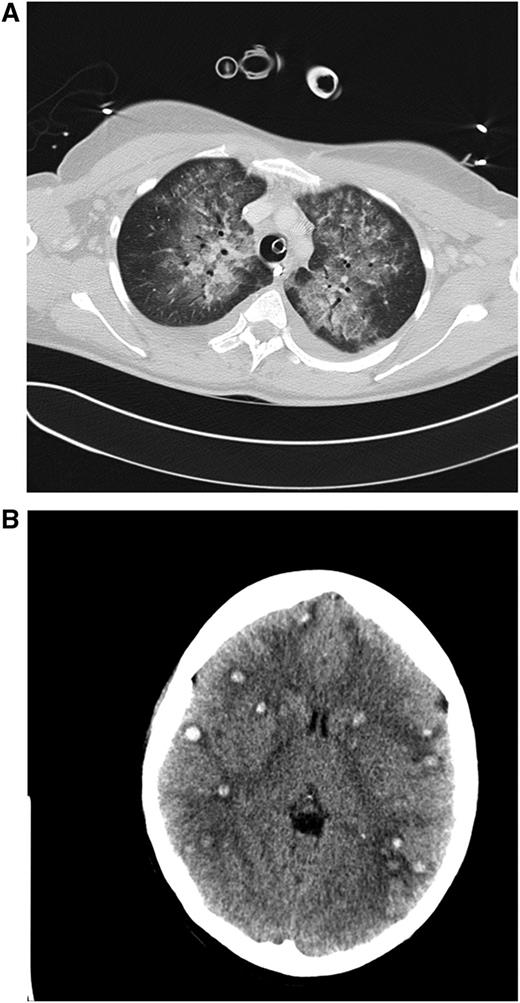

Clinical case 1. A 42-year-old woman presented to her general practitioner with general weakness and tooth pain. Laboratory assessment showed a WBC count of 80 000/µL, hemoglobin of 6.4 mg/dL, and platelet count of 21 000/µL, which led her physician to make an immediate referral to the local hospital, where a differential blood count revealed 56% myeloid blasts. By that time, the patient was in stable clinical condition with a minimally elevated C-reactive protein of 20 mg/L. She was put on 4 g hydroxyurea (HU) and planned for transferal to our hospital the next morning. During the night, she developed dyspnea requiring oxygen supply. We diagnosed an AML M4eo with inv(16) and started induction treatment with cytarabine plus daunorubicin (7 + 3) at a WBC count of 70 000/µL. Immediate leukapheresis was not possible because of the progressive dyspnea and the increasingly deranged coagulation status. By the next day, the WBC count had gone down to 19 000/µL, but the patient developed respiratory failure requiring mechanical ventilation. The computed tomography (CT) scan result was highly suggestive for leukostasis of the lungs (A), and cranial CT showed multiple focal supratentorial hemorrhages (B). During the next few days, respiratory indices improved, and the patient could be extubated. Early bone marrow response assessment showed a good response with leukemia-free hypoplastic marrow, and after regeneration of peripheral counts, a complete remission (CR) was diagnosed. The patient has currently completed consolidation chemotherapy and is in ongoing CR. The remarkable aspects of this case are (1) the fact that leukostasis developed rapidly even at a WBC count below 100 000/µL, possibly because of the monocytic nature of blasts11 ; (2) cytarabine alone led to a profound and rapid WBC reduction; and (3) the patient recovered from mechanical ventilation because the underlying leukostasis could be treated successfully. (A) Contrast-enhanced CT image (lung window) through the upper fields of the lungs demonstrates parenchymal infiltrates as well as diffuse ground-glass opacities suggestive for leukostasis and myeloblast infiltration. There is sparing of the lung periphery. Note also bilateral pleural effusions. Respiratory failure required mechanical ventilation support as indicated by the endotracheal tube. A central venous catheter in the right brachiocephalic vein and nasogastric tube in the esophagus can be seen. (B) Horizontal plane of native cranial CT scan demonstrating multiple hyperdense lesions in both brain hemispheres indicating hemorrhagic lesions. Accompanying cerebral edema is characterized by loss of gray-white matter differentiation, compression of lateral ventricles, and effacement of sulcal spaces.